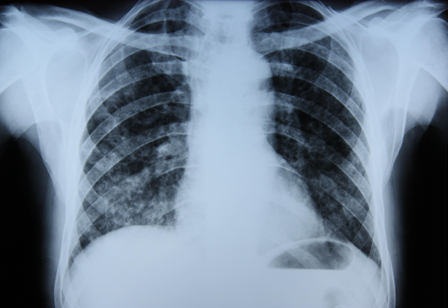

Radiografia torácica

[Figure caption and citation for the preceding image starts]: Radiografia torácica mostrando tuberculose pulmonar com cavitaçãoDo acervo pessoal do Dr. M. Narita, Departamento de Medicina Pulmonar e Intensiva, Universidade de Washington [Citation ends].